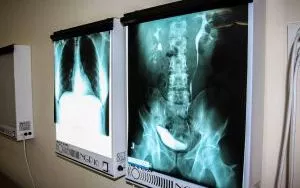

Technik elektroradiolog świadczy usługi medyczne w zakresie elektroradiologii w zakładach i pracowniach diagnostyki obrazowej, elektromedycznej, medycyny nuklearnej i radioterapii. Jego głównym zadaniem zawodowym jest wykonywanie zleconych przez lekarza badań i terapii oraz przygotowanie ich wyników do oceny. Do realizacji ww. zadania wykorzystuje: promieniowanie jonizujące, izotopy promieniotwórcze, zjawisko rezonansu magnetycznego, prąd elektryczny, ultradźwięki.

- wykonywać określone badania i zabiegi z diagnostyki obrazowej (m. in. zdjęcia RTG, badania mammograficzne, badania TK i MNR),

- Diagnostyka obrazowaPoznasz różne metody diagnostyki człowieka.

- RadiodiagnostykaPoznasz różne schorzenia rozpoznawane przy pomocy promieniowania rentgenowskiego oraz pola magnetycznego.

- Diagnostyka obrazowa - ćwiczeniaPoznasz sposoby układania pacjenta i wykonywania badań np. RTG, TK, MR.